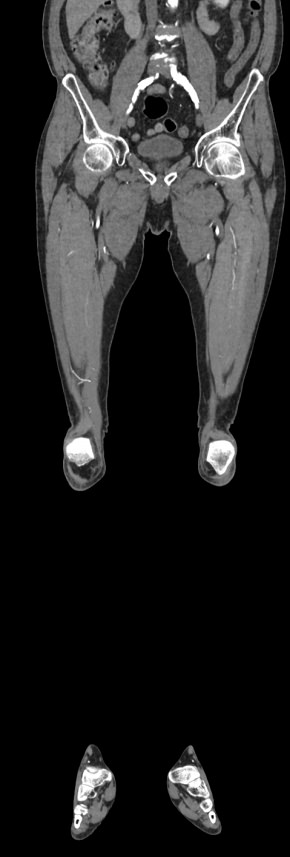

Мультиспиральная компьютерная томография является современным методом обследования сосудистой системы нижних конечностей. Такое исследование по-другому называется КТ-ангиография. Методика позволяет с помощью рентгеновского излучения получить посрезовые снимки и после цифровой обработки создать объемные модели кровеносной системы обеих ног.

В наших медицинских центрах КТ-ангиография нижних конечностей выполняется на современных мультиспиральных компьютерных томографах экспертного уровня TOSHIBA AQUILION. Аппараты послойно сканируют область исследования, одномоментно выполняя множество тончайших срезов. В результате получаются снимки высокого качества и трехмерные модели с изображением даже мелкой сосудистой сети нижних конечностей. При этом методика скоростного мультисрезового сканирования обеспечивает минимальную дозу рентгеновского облучения для пациента.

• КТ сосудов от бифуркации аорты до коленного сустава (оценивается нижняя часть брюшной аорты, разветвление аорты, подвздошные артерии, бедренные и подколенные артерии)